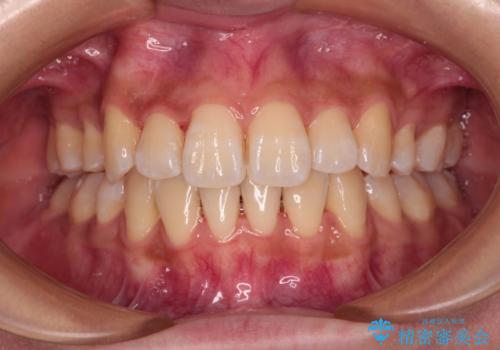

- 上の前歯の出っ歯と閉じにくい口元を気にして来院された患者様です。

口元を積極的に引っ込めるために、上顎左右の小臼歯1本ずつ抜歯することとしました。

突出していた口元がスッキリと仕上がり、患者様には大変満足していただきました。